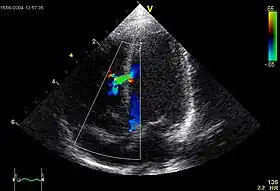

An abnormal echocardiogram: Image shows a midmuscular ventricular septal defect. The trace in the lower left shows the cardiac cycle and the red mark the time in the cardiac cycle when the image was captured. Colors are used to represent the velocity and direction of blood flow.